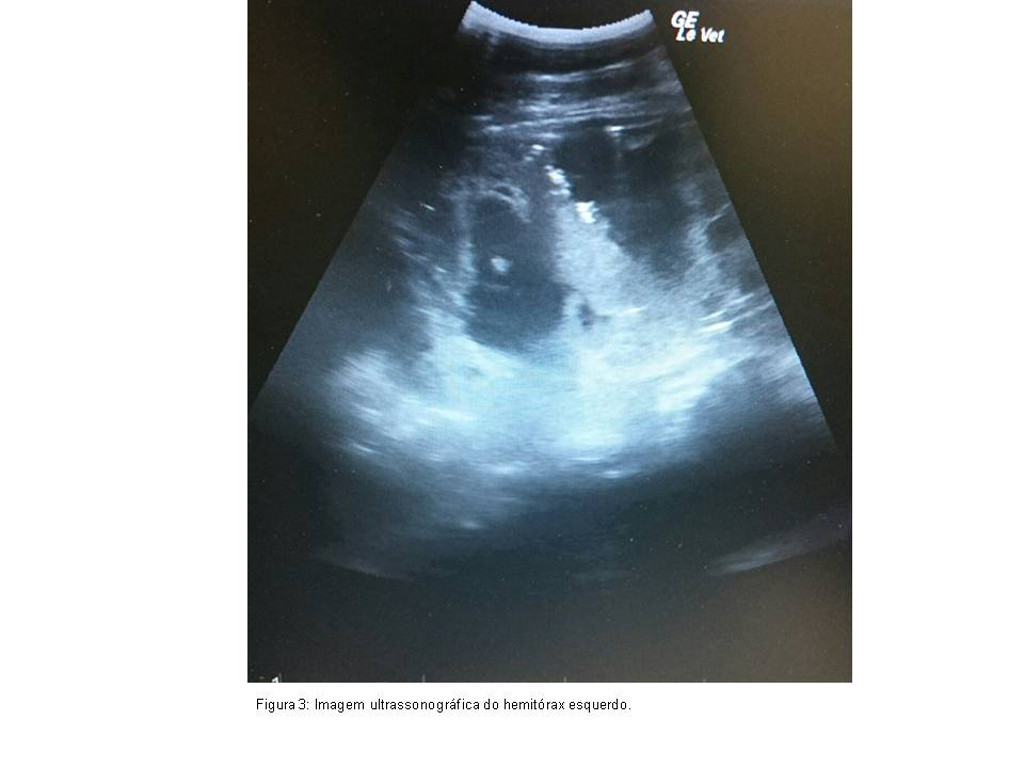

Foram prescritos Bryonia alba 6CH, três vezes ao dia e Echinacea angustifolia 6CH na mesma frequência. Posteriormente optou-se pela inclusão de Phosphorus 6CH uma vez ao dia. A drenagem por toracocentese (Figura 3) era efetuada quando ocorria grande acúmulo de líquido visualizado através de exame ultrassonográfico. Após 40 dias deste tratamento foi submetida ao procedimento de toracotomia do hemitórax esquerdo para retirada de conteúdo fibrinóide e líquido seroso e para efetuar lavagem com solução de permanganato de potássio duas vezes ao dia. O uso de fenilbutazona 4g foi mantido em quadros febris alternando com dipirona sódica 25mg/Kg. Devido à persistência da febre introduziu-se TK 30CH em dias alternados.

Figura 3